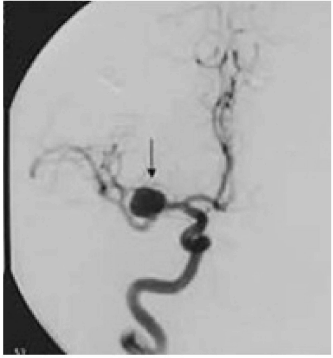

Exames de angiografia são utilizados frequentemente para a detecção de alterações vasculares. Os aneurimas são alterações vasculares importantes, causados por fraqueza da parede vascular.

Observando o exame de angiografia por ressonância magnética acima, podemos concluir que a seta indica um aneurisma: